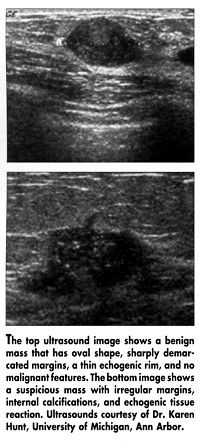

Eleven dedicated breast-imaging radiologists performed ultrasound examinations and classified the masses prospectively as benign or suspicious using a "gestalt" evaluation technique. According to Dr. Hunt, the gestalt technique is difficult to define, but is based on the radiologists’ experience. The masses were also classified based on the previously published Stavros criteria that define how a benign or malignant mass might appear on ultrasound (see Figure).

The Stavros criteria was slightly less effective in identifying benign masses, classifying 24 (29%) of the 82 benign masses correctly, but, as with the gestalt method, all 55 of the cancers were classified as suspicious. Therefore, this method would have prevented 24 biopsies, reducing the rate by 18%. The advantage of the Stavros criteria, she said, is that specific sonographic descriptors can be more easily replicated from institution to institution.